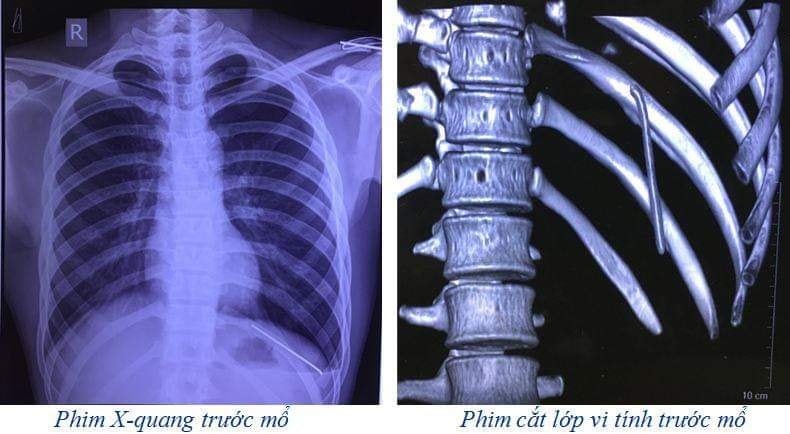

Sau khi thăm khám, các bác sĩ đã chỉ định chụp X-quang và cắt lớp vi tính lồng ngực. Kết quả phim cắt lớp vi tính lồng ngực cho thấy có một dị vật dạng kim khí trong KMP trái, tràn khí KMP trái.

| Hình ảnh chụp X-quang và chụp cắt lớp cho thấy đinh đã rơi vào khoang màng phổi. |